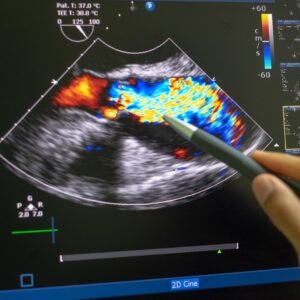

Follow-up follicle monitoring in the same cycle uses transvaginal ultrasounds to track the growth and maturation of ovarian follicles, starting with a baseline scan on days 2-3 of the menstrual cycle and continuing with frequent scans (every 1-3 days, then daily) until a dominant follicle reaches 18-22mm and is ready for ovulation.

This monitoring allows doctors to pinpoint the fertile window for natural conception, time fertility treatments like IUI or IVF, or administer a trigger shot at the optimal time to induce ovulation.